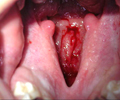

Paladar secundario

Del paladar blando